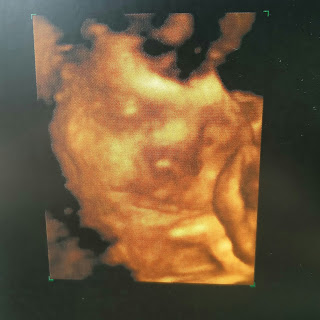

Última ecografia oficial e fotos 3D